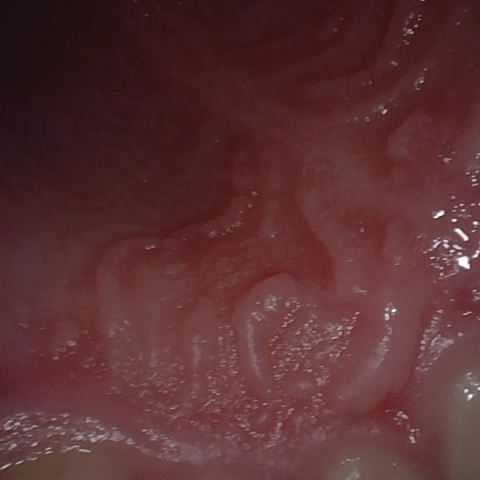

NHD39990

Annotated as "Good"